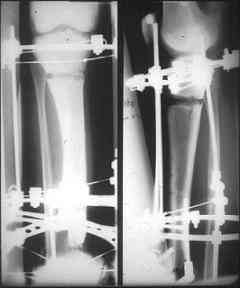

отделяемое. #1;#2. Стержневой апп. снят, наложен апп. Илизарова, дренажно-ирригационная система промывки раны. #3; #4. После стихания инфекции,

аппаратом постепенно создана рекурвация для сближения контактов мышц (сухожилий) передней группы голени. #5;#6. Наложен шов на сухожлилия М.